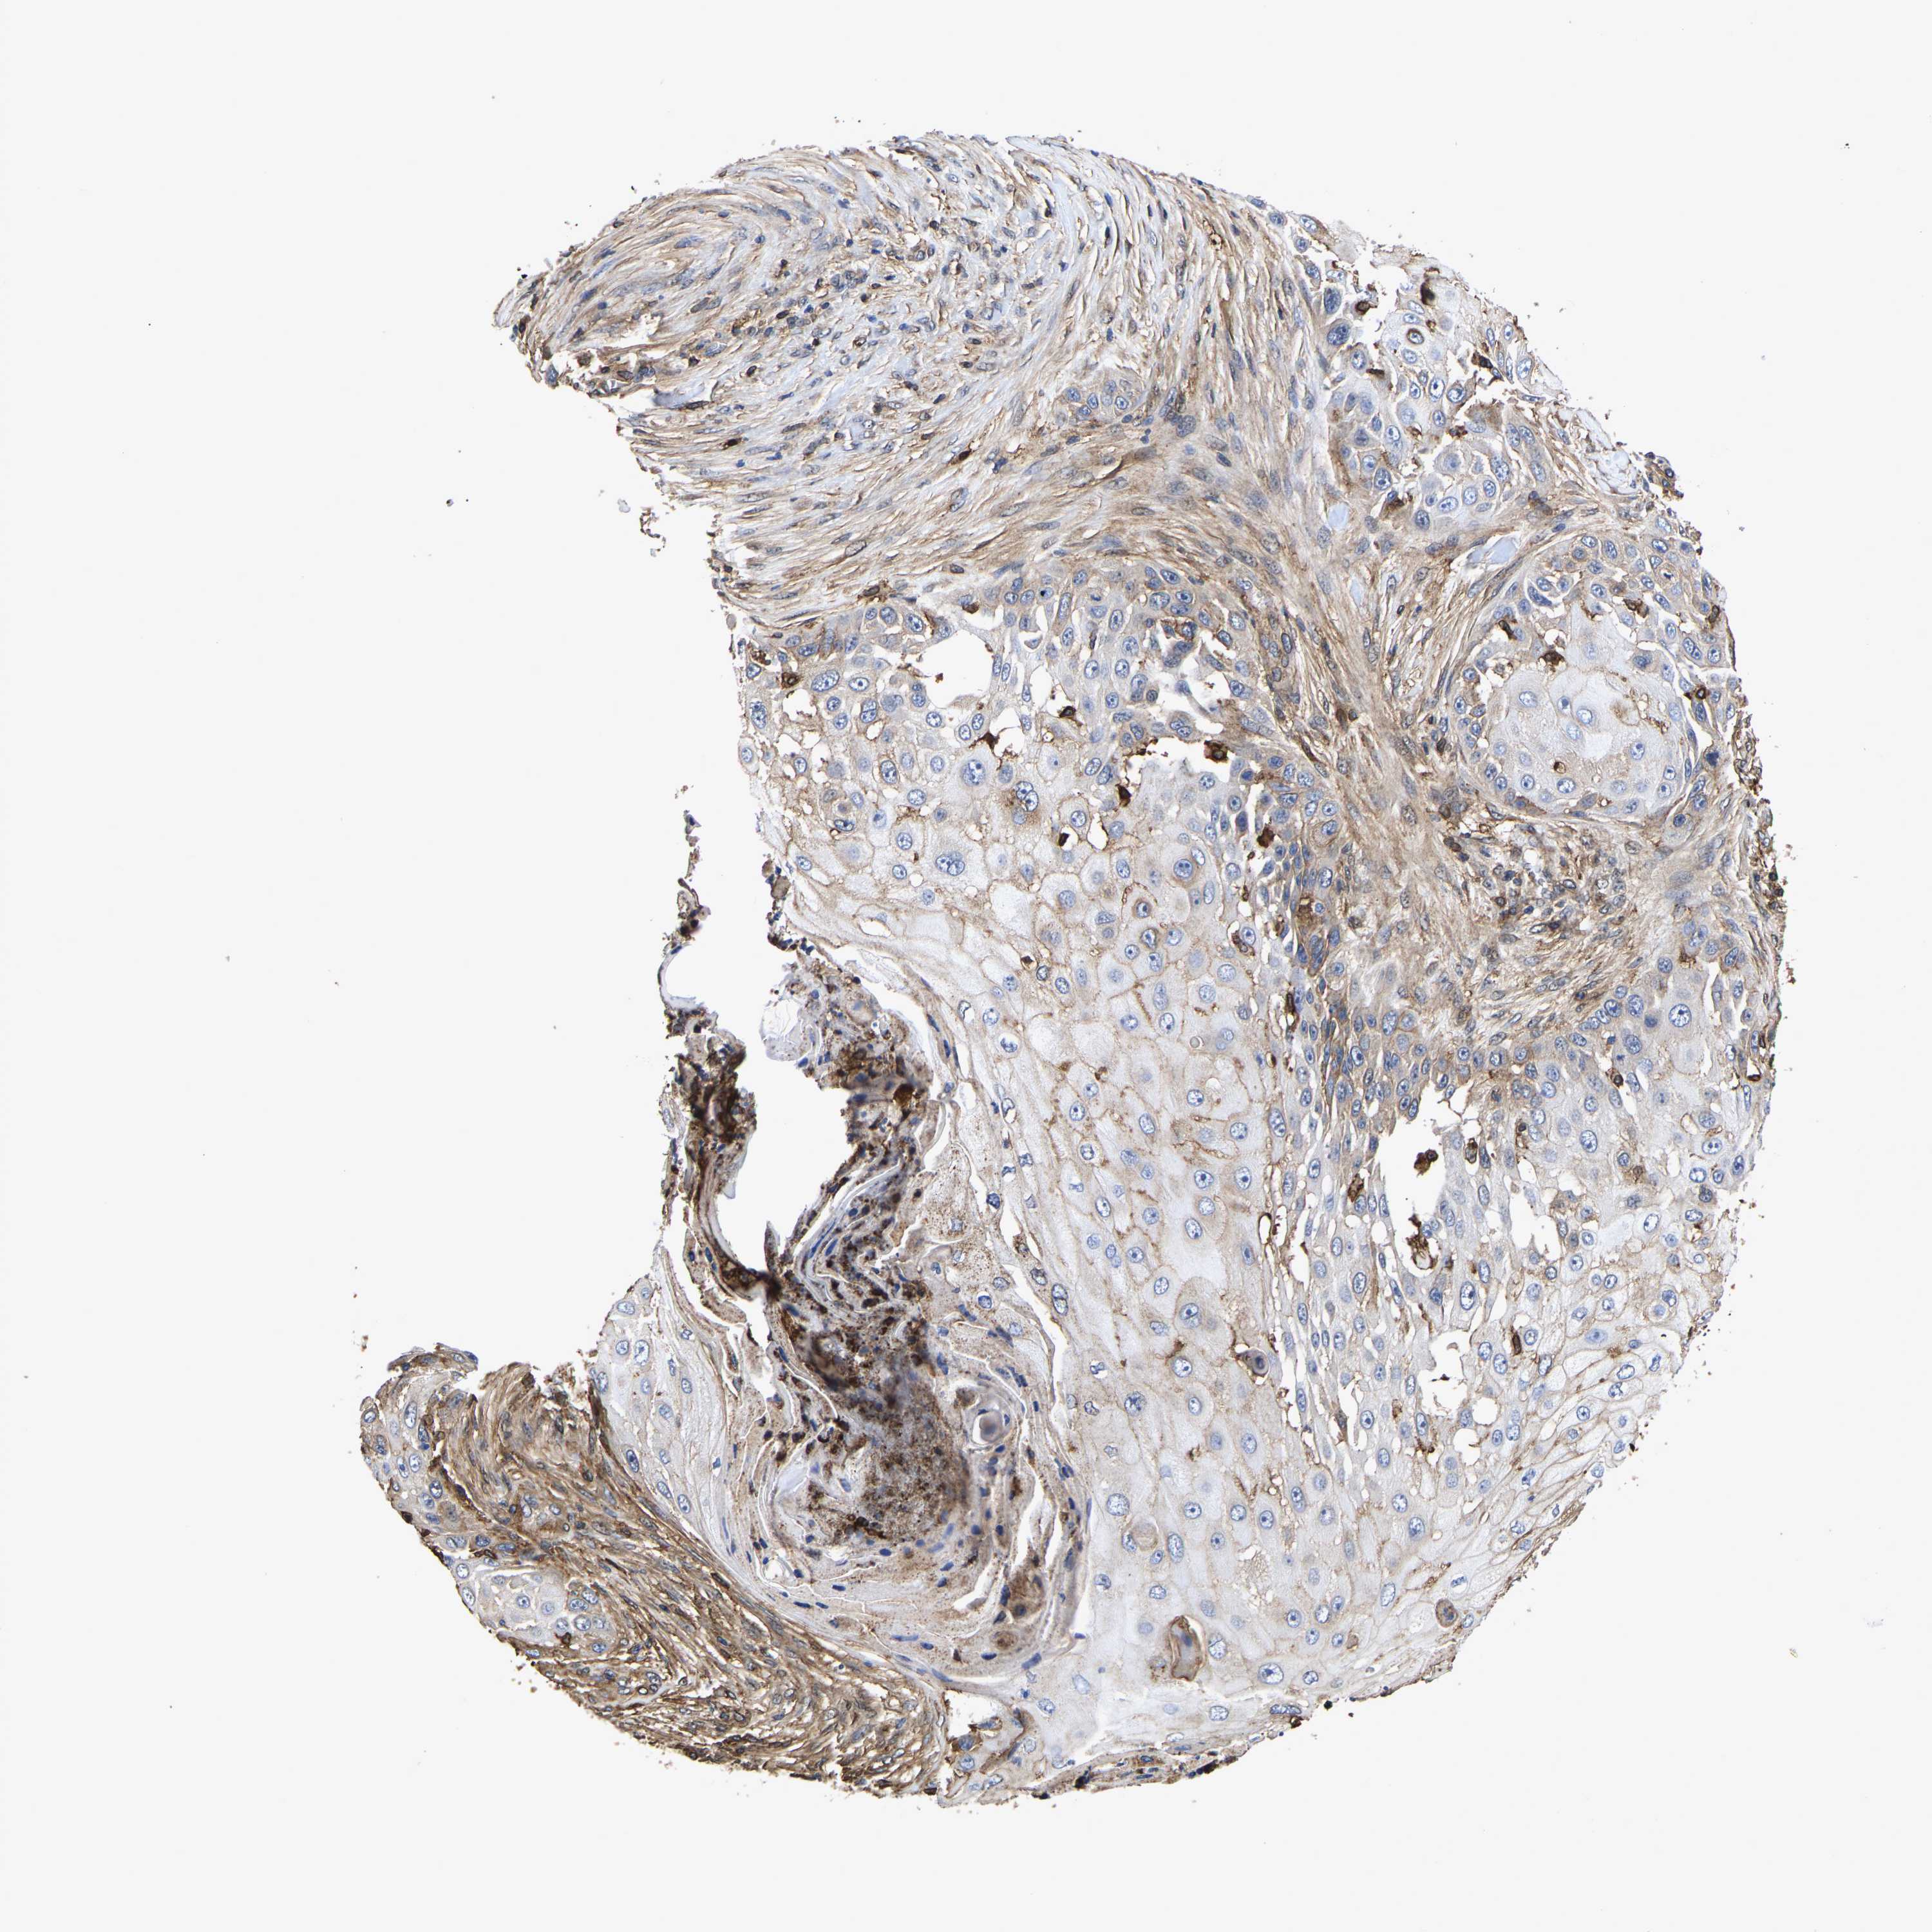

Basal cell and squamous cell cancer

SKIN CANCER - Protein expressioni

A mouse-over function shows sample information and annotation data. Click on an image to view it in a full screen mode. Samples can be filtered based on level of antibody staining by selecting one or several of the following categories: high, medium, low and not detected. The assay and annotation is described here.

Antibody stainingi

Antibody staining in the annotated cell types in the current human tissue is reported as not detected, low, medium, or high, based on conventional immunohistochemistry profiling in selected tissues. This score is based on the combination of the staining intensity and fraction of stained cells.

Each image is clickable and will lead to virtual microscopy that enables deeper exploration of all samples and also displays staining intensity scores, fraction scores and subcellular localization as well as patient and tissue information for each sample.

Antibody HPA018844

Staining

High

Intensity

Strong

Quantity

>75%

Location

Nuclear

Squamous cell carcinoma, metastatic, NOS